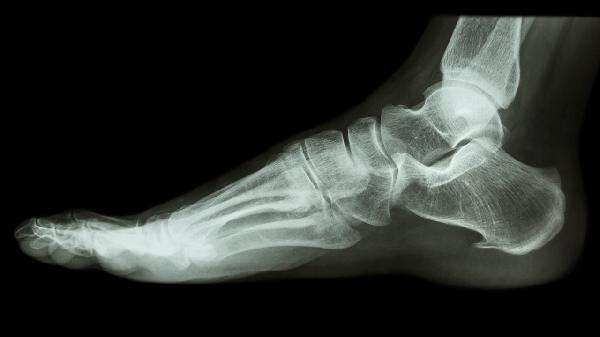

小脚趾骨头疼痛是什么原因

小脚趾骨头疼痛可能由外伤、鞋子挤压、痛风性关节炎、拇外翻或应力性骨折引起,需根据具体病因采取针对性治疗。

5、应力性骨折:

长期跑步或跳跃导致第五跖骨微小骨折,表现为渐进性疼痛。需停止运动4-6周,严重位移需手术内固定。